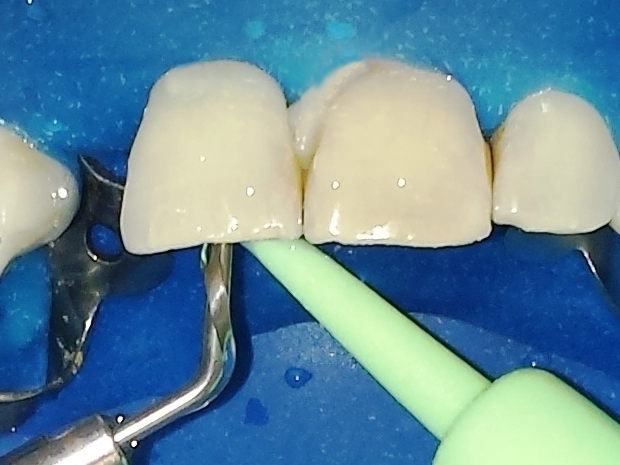

Paciente do gênero masculino, 32 anos, apresentou-se com quadro clínico de necrose pulpar dos elementos dentais 11 e 12 (figura 1), associado à presença de reabsorção interna, sendo submetido ao tratamento endodôntico em ambos os elementos.

- Figura 1